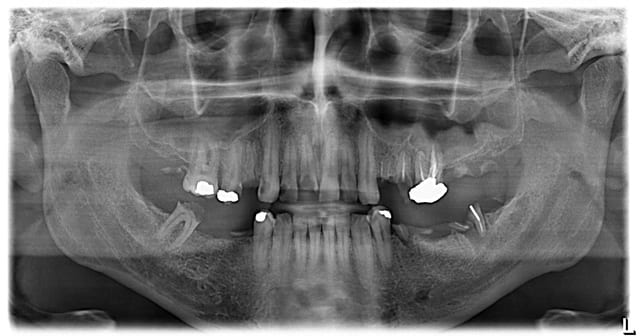

Cetains patients sont adorables: quand ils entrent pour la première fois, et nous parlent de "check-up", on se dit "oh, une hygiène parfaite, et on ne trouvera rien, meme pas un peude métal"...Puis deja sur le pano, les choses se gatent...Et lors de l'examen endobuccal, la, la situation parait un peu plus compliquée que prévu...Le prat le leur explique, et eux: "oh, vous savez, on a toujours eu les dents gatées dans la famille, mais comme ca ne fait pas mal...."

Bouchewc dsjkae - Eugenol